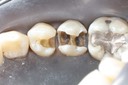

Kyle Chock #14 caries removal